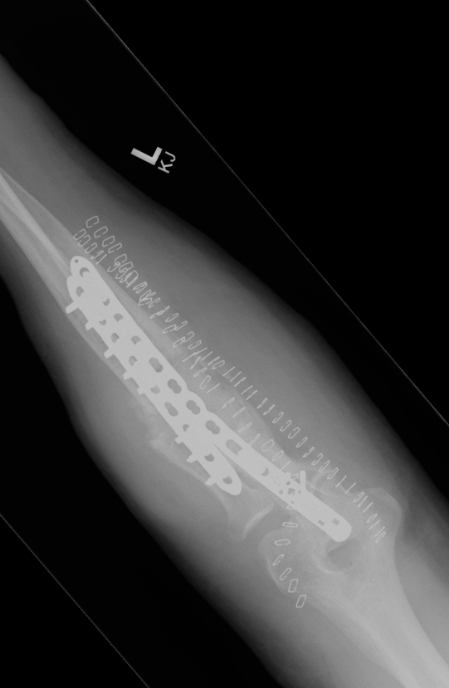

ORIF with DCP plates

Fixation with DCP plates

Options

Revision compression plating + drill intra-medullary canals + autograft

Results

- 35 forearm nonunions treated with revision compression plating and bone grafting

- average defect 2 cm

- 100% union